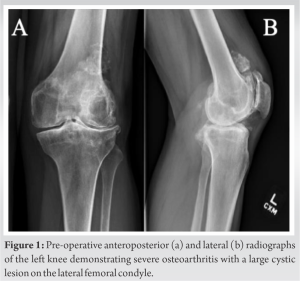

CT showed a large lytic lesion involving most of the lateral femoral condyle, with no aggressive features, most consistent with a benign bone cyst (Fig. 2). After extensive discussion of non-surgical and surgical options, the patient elected to undergo left robotic-assisted TKA, including bone cyst debridement and grafting. The decision to use a cementless knee prosthesis in this case was driven by the patient’s relatively young age, the need to preserve bone stock, and the potential benefits of osteointegration. The possibility of requiring revision TKA implants was discussed.

Extensive pre-operative planning was undertaken to address the technical challenges faced by this case. Planning objectives were to aim for a CR construct to minimize bone resection (Fig. 3). Alternative plans were made for stemmed posterior stabilized (PS), and total stabilized (TS) constructs with the use of femoral stem as needed. Pre-operative CT scanning was performed using the standard RA-TKA protocol (Stryker Mako, Mahwah, NJ). CT characterized a cystic lesion measuring 5 cm in its axial dimension. The resulting anatomical models demonstrated severe medial and lateral compartment osteoarthritis with genu valgus alignment.